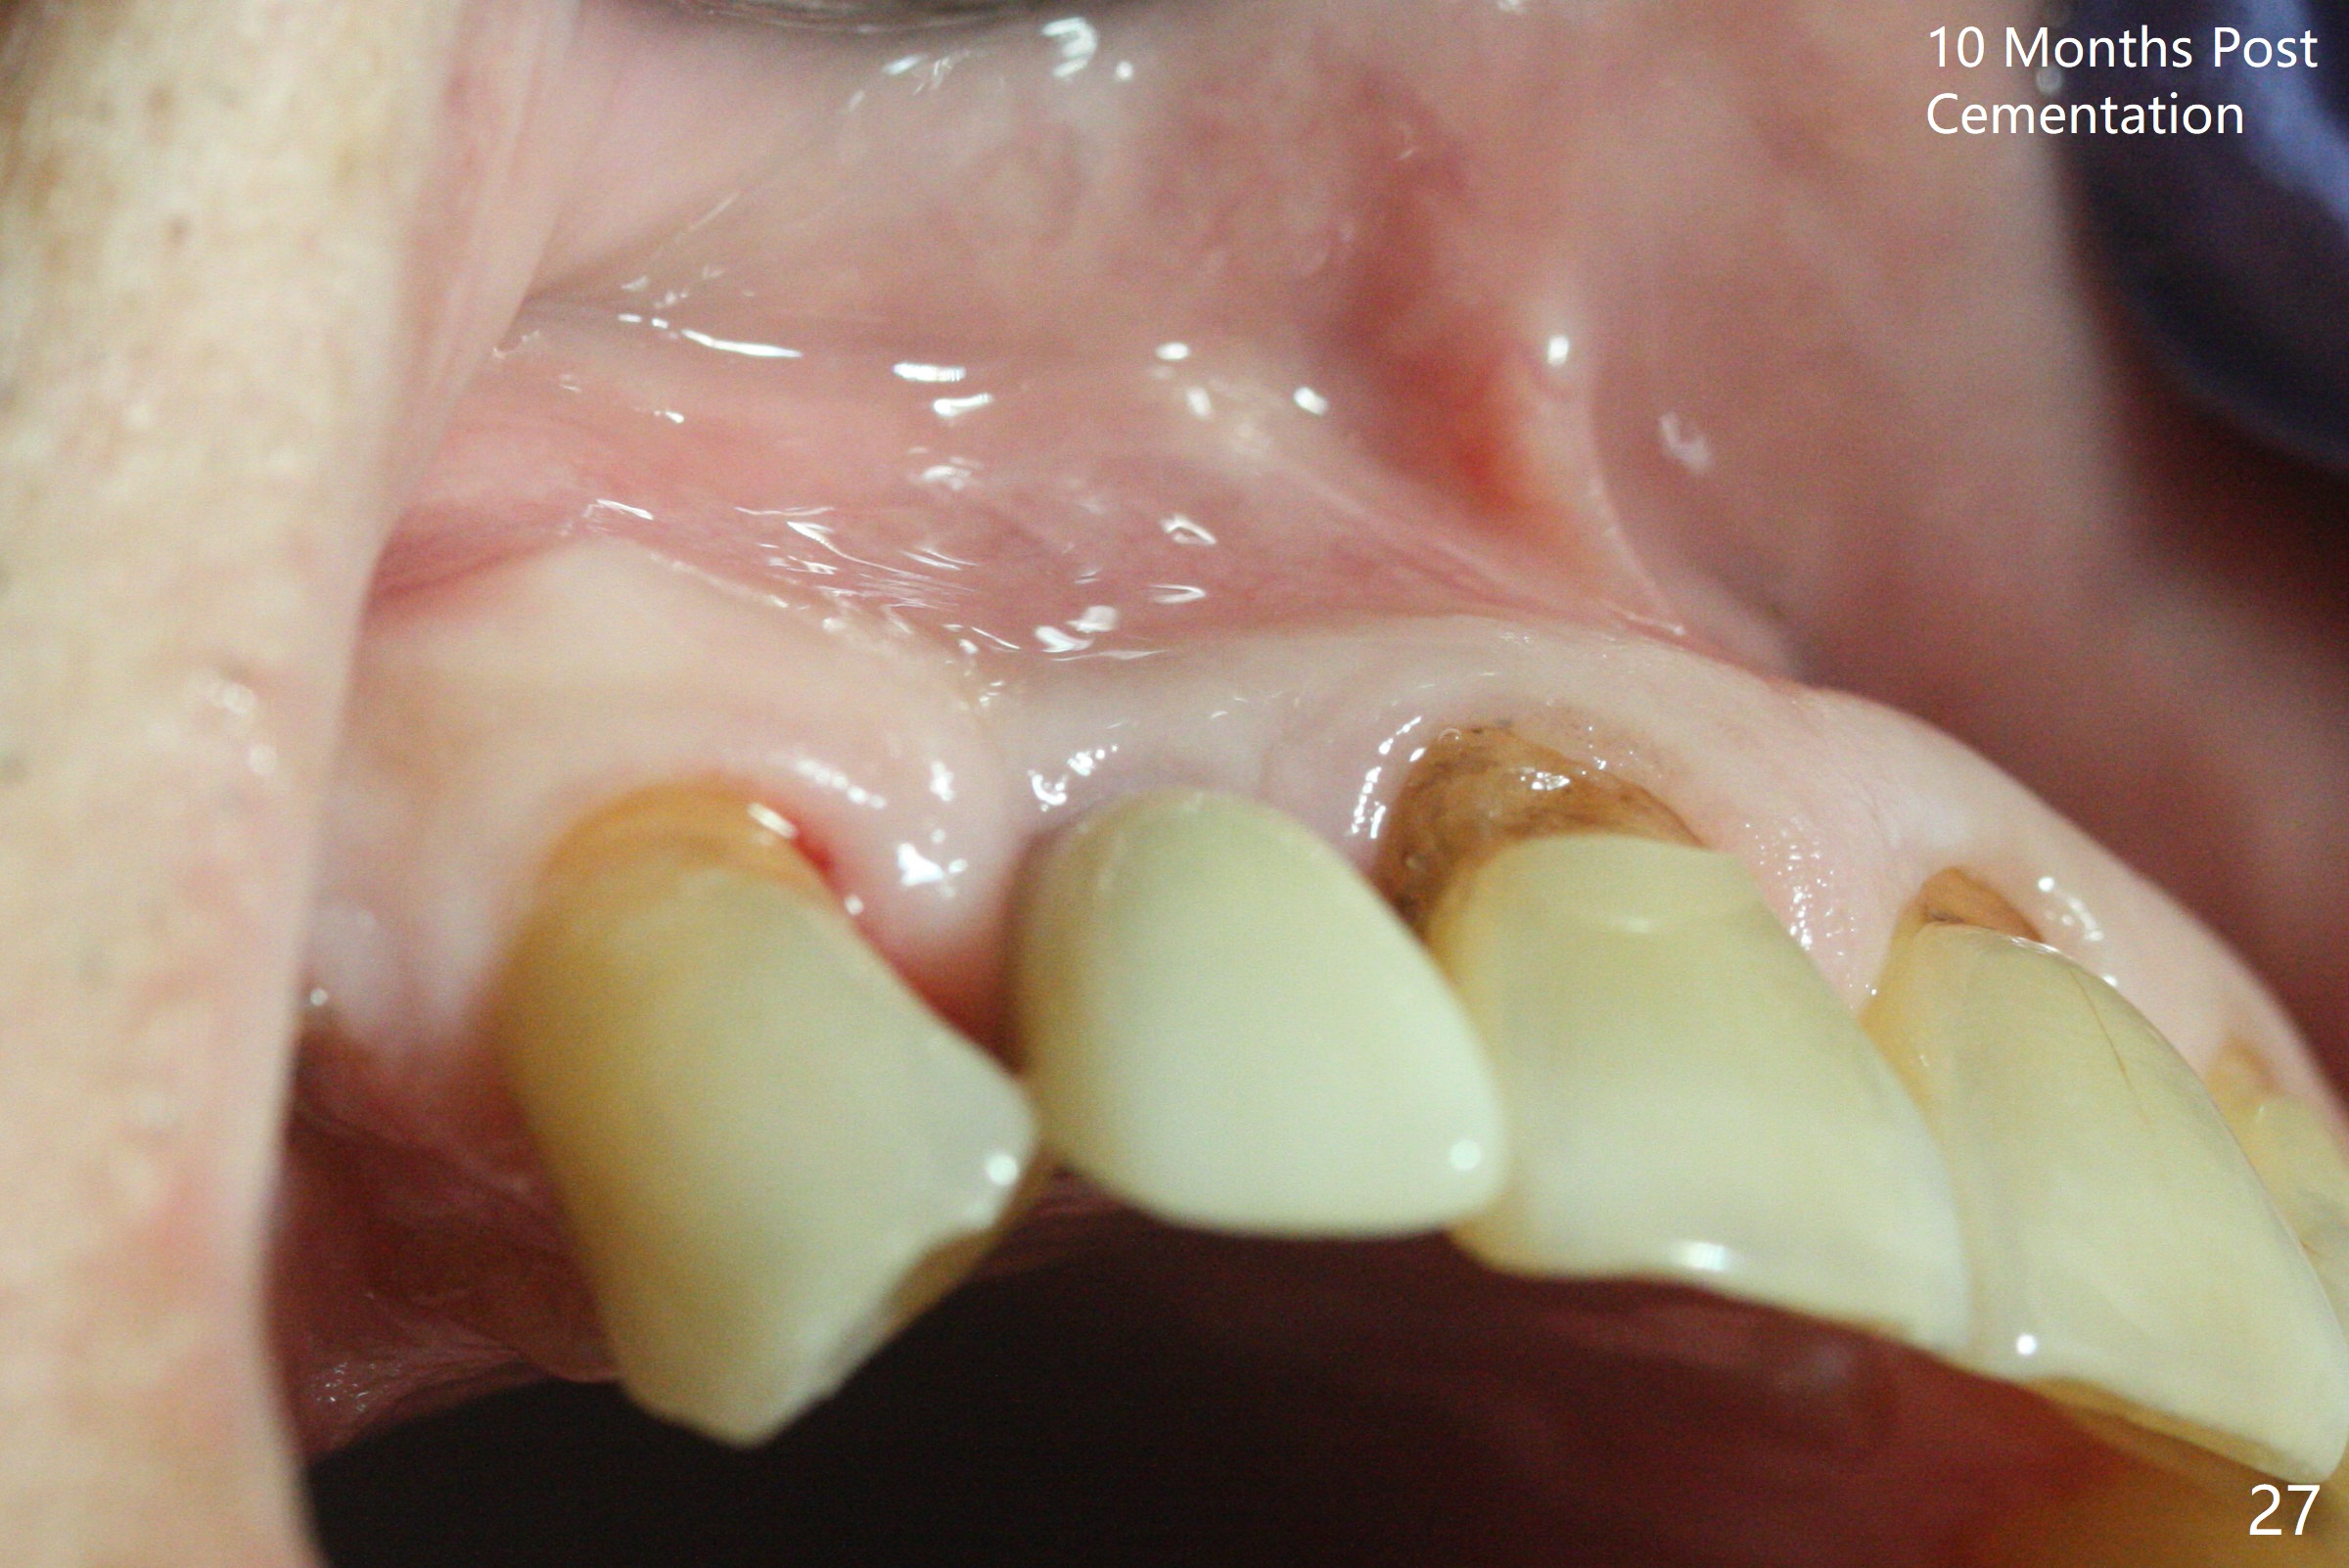

An apical abscess is present when the patient returns for immediate implant at #7 (Fig.1 *); a 2nd challenge is deep bite. After smooth extraction, the apical buccal plate is found to be perforated. Following debridement, a piece of gauze is placed in the apical defect for hemostasis, while osteotomy is initiated palatal (Fig.2). The apical defect seems to be extensive (Fig.3 yellow dashed line). A new trajectory is intended (red arrow) without much success. Before implant placement, bone graft is placed in the apical defect defect area, while a drill (Fig.4 D) is inserted in the finished osteotomy (Fig.5 O). In spite of seemingly large apical defect, the buccal crest bone exists (Fig.4 x). A 3x14(2) mm 1-piece implant is placed with stability; the first round of bone graft is apparently around the apical portion of the implant (Fig.6 *). The coronal end of the implant has to be adjusted several times buccopalatally to accommodate the deep bite. A 2nd round of bone graft following an immediate provisional closes the coronal space of the socket (Fig.7 *). CT will be taken to show the bone graft to repair the buccal plate defect when the patient returns for postop follow-up. In fact the defect is minimal in CT a month ago. The fistula does not disappear 1 week postop, but it is non tender (Fig.8). The patient complains of asymptomatic swelling in the right nostril. CT shows that the large buccal perforation is repaired with large amount of bone graft (Fig.9,10 *). It would be nicer to place the implant slightly more buccal apically (Fig.11 red lines; Fig.12 (preop design)). The buccoapical fistula disappears nearly 1 month postop (Fig.13). The apparently "lifeless" bone graft seems to be harmonious with the surrounding tissue (Fig.14). The periimplant gap reopens with implant mobility nearly 4 months postop (Fig.15), which is related to micro-movement associated with the immediate provisional. The latter is removed. A larger 2-piece implant will be placed in a 2-staged manner if needed (Fig.16). In fact the 3x14 mm straight 1-piece implant (Fig.17) has no mobility when it is retightened, but the trajectory remains buccal. Incision shows that there is no implant thread exposure. A 3x14 mm 15 degree angled 1-piece dummy implant is able to establish the correct trajectory, but there is no occlusal clearance (Fig.18). Micromovement during osteointegration may recreate loosening. Finally using Lindamann bur, the osteotomy is changed so that a 3.5x13 mm 2-piece implant does not need an angled abutment to establish occlusion (Fig.19). There is one palatal thread exposure. Allograft is placed circumferentially, followed by Human Amnion-Chorion Allograft and Collagen Plug. The wound does not heal 8 days postop (Fig.20), as related to the age (79 years old)? The wound appears to heal with a membrane on the surface (Amnion-Chorion one?) 3 weeks postop (Fig.21). The ridge looks wide 3.5 months postop (Fig.22,23). A 4.5x5.5(3) mm appears to be seated incompletely with a gap between the abutment and the implant (Fig.24<). A provisional is fabricated after heavy palatal reduction. Two months later, the provisional fractures. After repositioning the abutment with complete seating and torque (Fig.25), impression is taken. Although the buccal plate is concave, the gingiva remains healthy 10 months post cementation (Fig.26,27).